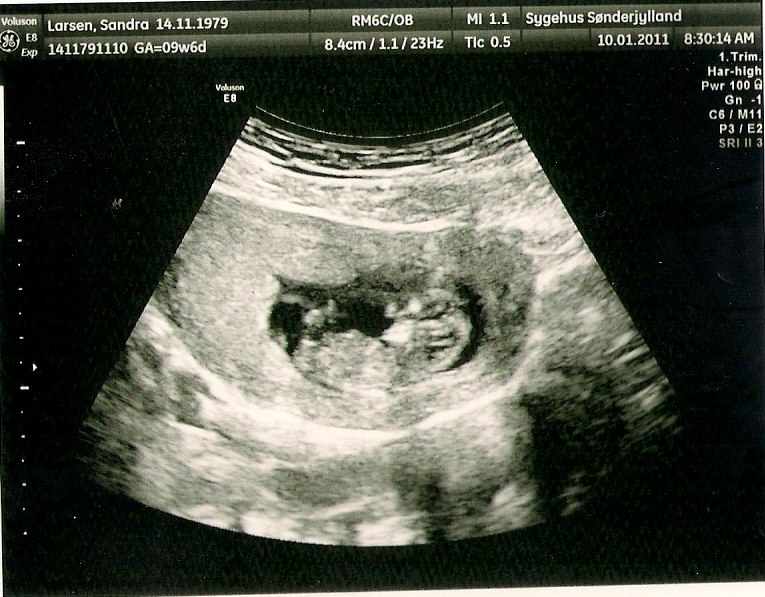

så har jeg været til min kontrol scanning idag som jeg frygtede så meget... og IGEN helt uden grund.... den lille spire havde det fint

og hun sagde jeg idag var 10+4...

her er den lille bitte spire på 4cm